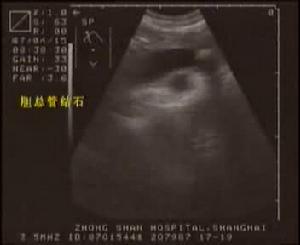

3.超聲發現膽囊內有結石,膽囊腫大、積液,壁增厚或萎縮;口服膽囊造影證實膽囊內結石。超聲診斷正確率可達95%以上。

其他輔助檢查:影像學檢查是當前賴以確診膽囊結石病的主要手段,超聲常是第一線的檢查手段,可以發現膽囊內結石、膽囊壁增厚、膽囊缺乏收縮,結果常是準確可靠的。其他的檢查方法則往往根據超聲檢查結果而確定是否進一步採用。在X線平片上,約20%的膽囊結石因含鈣量高,可呈陽性影像。由於結石陽性率低,肝膽區的X 線平片已不作為臨床診斷要求。但X 線平片可顯示腫大的膽囊及炎性腫塊的軟組織影以及在氣性膽囊炎時可見膽囊內及膽囊周圍的氣體影。此外,一些間接的X 線徵象,往往有助於急性膽囊炎的診斷:①膽囊下方小腸的擴張、充氣等反射性腸淤積症;②膽囊區軟組織陰影增大;③腹膜的刺激徵象,如右側的腹膜脂肪線模糊或消失、右側膈肌抬高;④右側胸膜反應性積液或右下肺葉盤狀肺不張等。當膽囊管通暢、膽囊的濃縮功能尚好時,口服法膽囊造影可顯示膽囊內結石的負影,準確率可達95%。若膽囊管通暢,靜脈法膽囊造影可顯示膽囊內的結石負影。CT 圖像上可見膽囊壁厚,囊內有結石和膽汁沉積物。口服膽囊造影劑CT 掃描檢查,可增加對結石的分辨力。